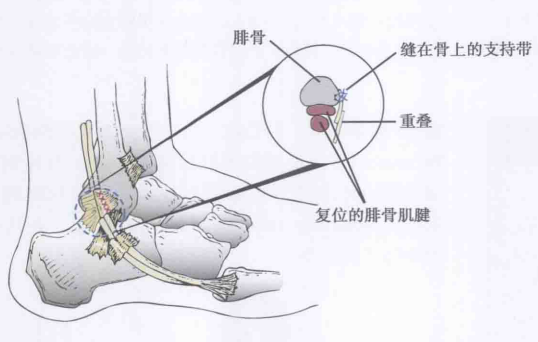

如果保守治疗不成功或慢性不稳定,建议进行手术干预。建议对急性或慢性脱位的精英运动员进行手术。运动员的手术治疗应常规包括腓骨肌沟加深法。

腓骨肌腱脱位的手术类型有:

③外踝腓骨肌沟加深法;

图源:Coughlin M,Saltzman C,Anderson R,et al. 曼氏足踝外科学 [M]. 第 9 版. 唐康来, 徐林, 译. 北京: 人民卫生出版社,2015:1915.

图源:Coughlin M,Saltzman C,Anderson R,et al. 曼氏足踝外科学 [M]. 第 9 版. 唐康来, 徐林, 译. 北京: 人民卫生出版社,2015:1915.

图源:Coughlin M,Saltzman C,Anderson R,et al. 曼氏足踝外科学 [M]. 第 9 版. 唐康来, 徐林, 译. 北京: 人民卫生出版社,2015:1915.

图源:Coughlin M,Saltzman C,Anderson R,et al. 曼氏足踝外科学 [M]. 第 9 版. 唐康来, 徐林, 译. 北京: 人民卫生出版社,2015:1915.

图源:Coughlin M,Saltzman C,Anderson R,et al. 曼氏足踝外科学 [M]. 第 9 版. 唐康来, 徐林, 译. 北京: 人民卫生出版社,2015:1915.